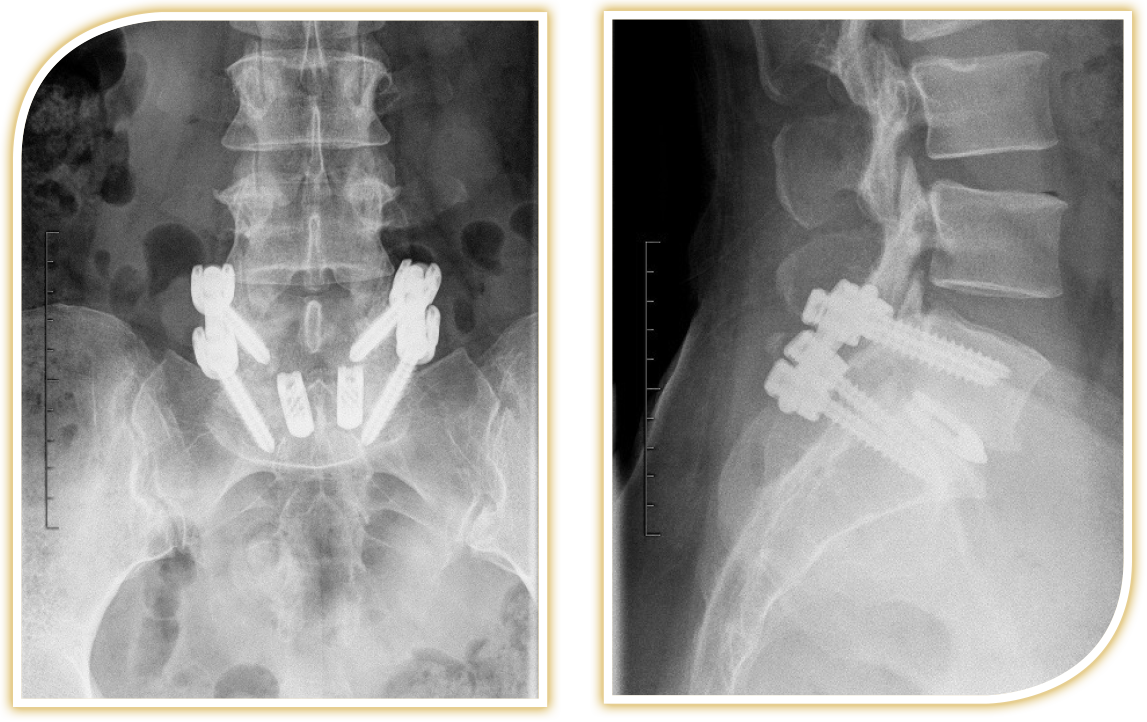

ALIF, Cage, Fusion, STLine, anterior, lumbal

Herniated disc of the cervical spine Neurosurgery, Inselspital Bern. Wirbelkörperersatz an der Halswirbelsäule (HWS) Bei der Operation werden Titan-Implantate (Wirbelkörperersatz-Cage und Platten) durch einen ventralen Zugang (an der Halsvorderseite) im Bereich der Halswirbelsäule eingesetzt Damit wird die Wirbelsäule stabilisiert und die Deformitäten ausgeglichen.